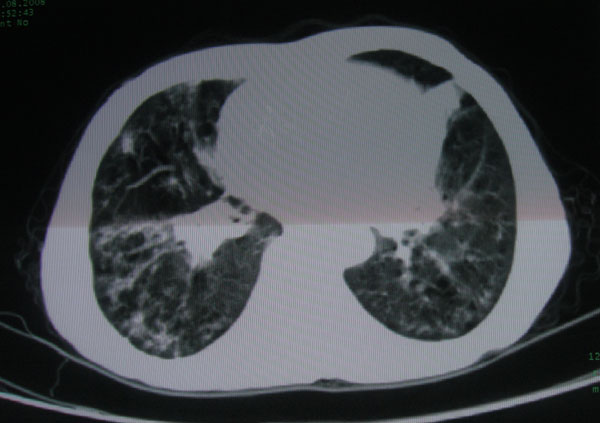

标题: CT15046:F59Y,咳嗽间断咳血丝痰就诊. [打印本页]

咳嗽\间断咳血丝痰就诊.

本例应该是“慢性疾病并发多种合并症”即:慢支并感染并支气管扩张征!结合病灶分布 形态分析,不除外合并“继发性肺结核”!

多考虑支气管扩张并感染,双下肺继发性肺结核不除外

慢性支气管炎伴全小叶型肺气肿、支气管扩张、感染、间质纤维化